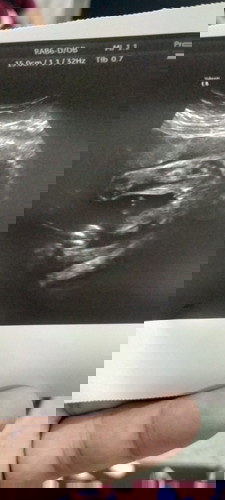

แบบนี้ผญ หรือผชค่ะ ช่วยดูหน่อยค่ะ

ลูกคนแรกค่ะแบบนี้ผมผญหรือผช ค่ะ

คล้ายผญ.ค่ะ คุณหมอได้บอกไหมคะว่าเพศอะไร ถ้าคุณหมอบอกแล้ว เชื่อคุณหมอเถอะค่ะ

ญ จ้าของเราเเบบนี้ ซาว3รอบแล้วหมอบอกลูกสาวจ้า

เราว่า ญ.นะค่ะ แต่หมอไม่บอกแม่หรอว่าเพศไหน

คิดว่าผญค่ะ ถ้าผช จะโด่เด่ออกมาแบบนี้ค่ะ

คิดว่าผู้ชายนะคะ เหมือนจู๋ โผล่มาเลย

น่าจะเป็นผู้หญิงนะค่ะ ดูจะจิมินะ

ก้ำกึ่งไปทาง ญ. ค่ะ ไม่โด่